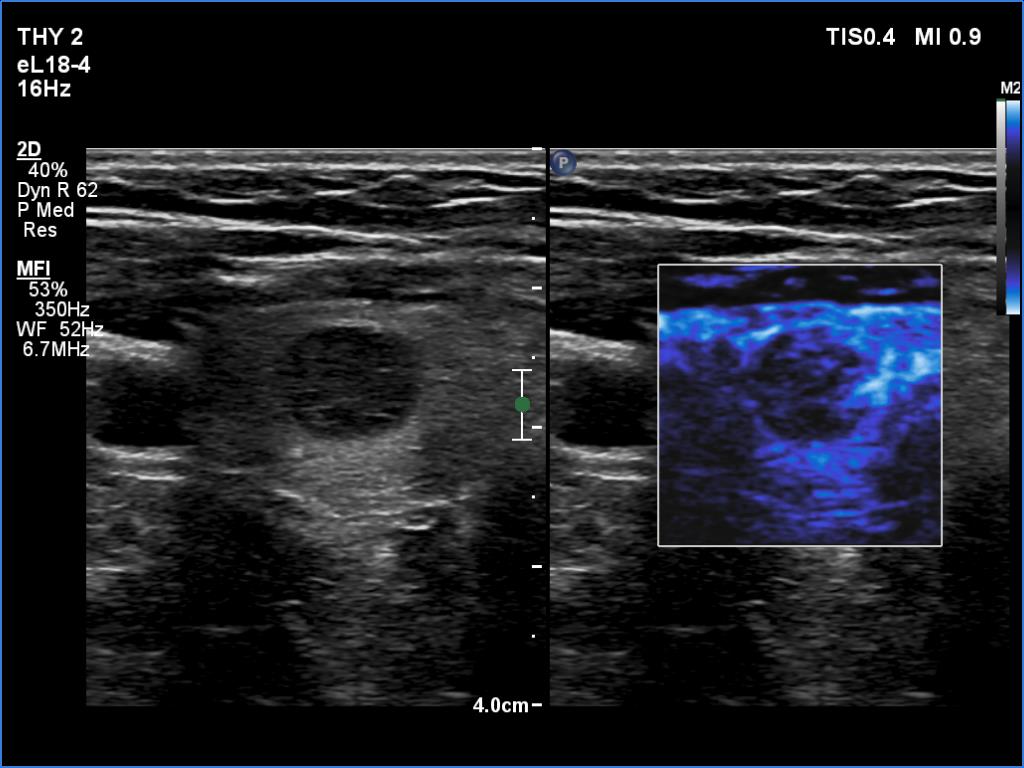

Ultrasonography. The thyroid was echonormal and presented several minimally-moderately hypoechoic areas. One of them, which was located in the central part of the right lobe was deeply hypoechoic and corresponded to pathological nodule. The other lesions seemed to be not true nodules but more active foci of thyroiditis.

Comment. It is worth comparing the deeply hypoechoic nodule with the other discrete lesions. The former has regular, sharp borders, and its echogenicity differs from other areas of the thyroid. These are the main clues of differentiation of a true nodule from a discrete lesion of Hashimoto's thyroiditis.